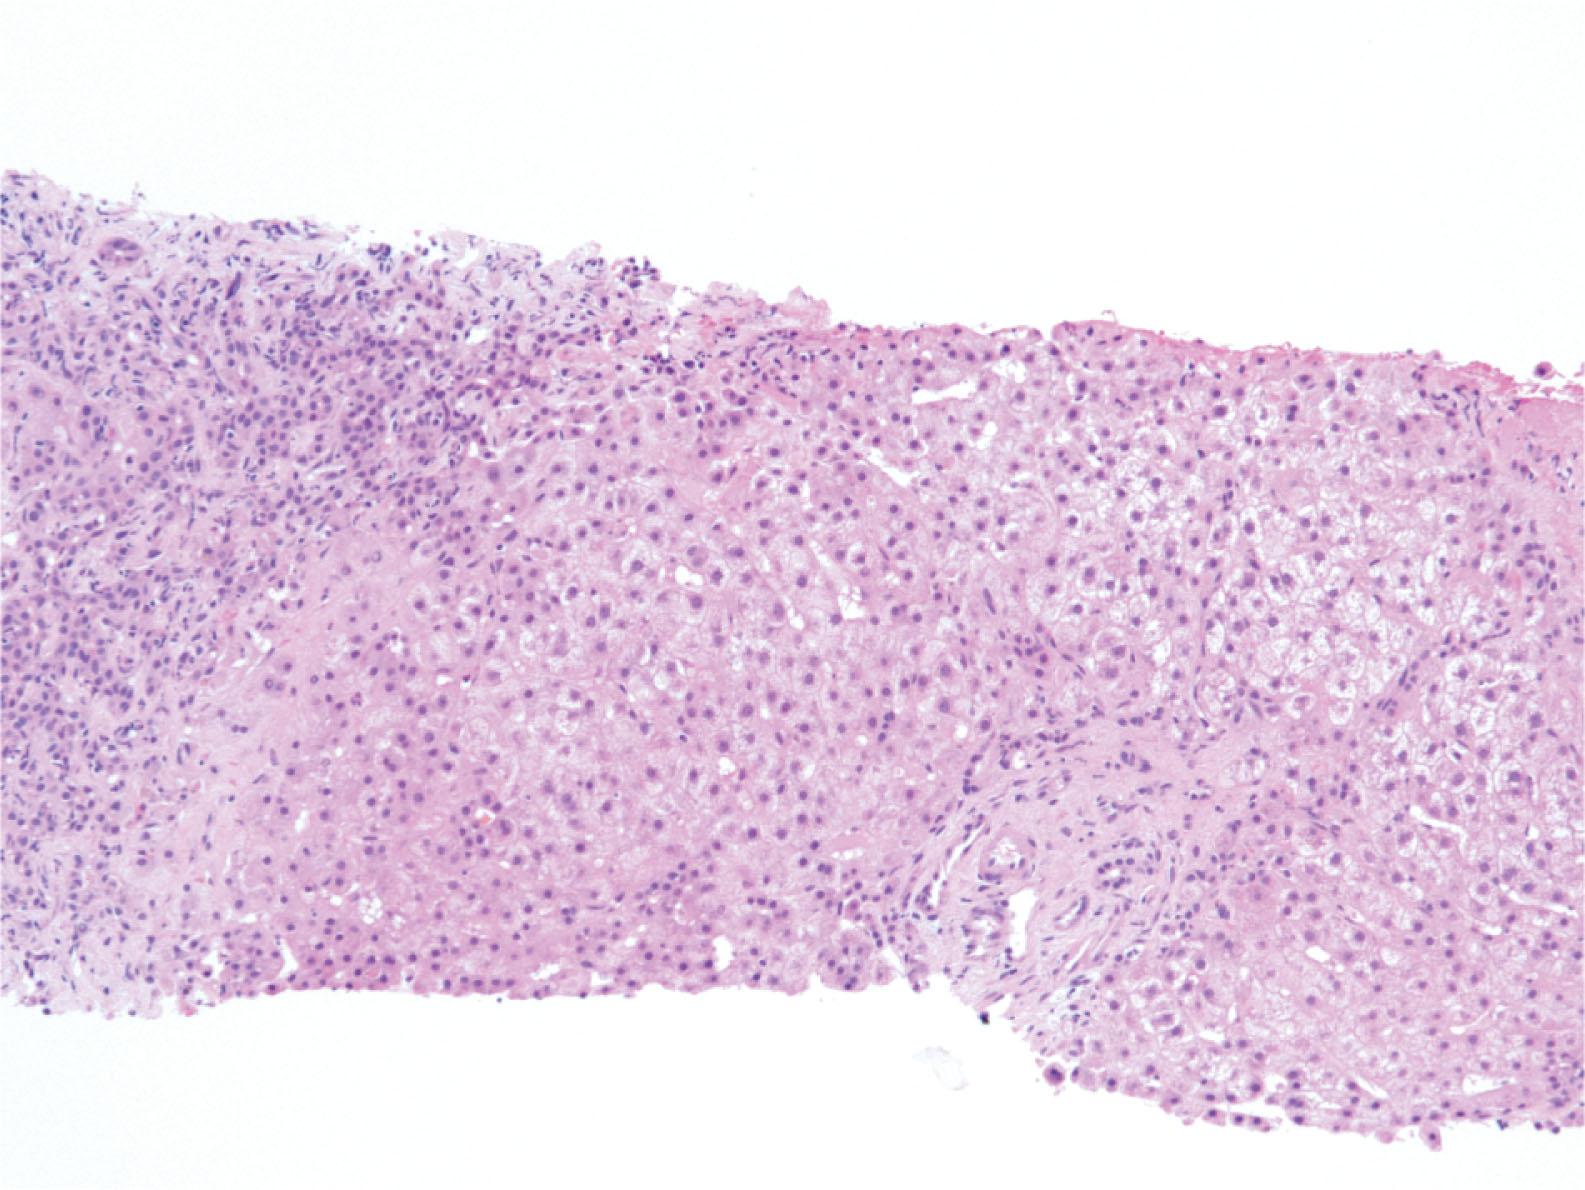

Figure 17.13, Diffuse swelling of hepatocytes with pale appearance and bile ductular proliferation, characteristic of early stages of fibrosing cholestatic hepatitis C.

Fibrosing Cholestatic Hepatitis

The FCH variant of HBV and HCV is an aggressive form of hepatitis that typically occurs in immunosuppressed patients. FCH is characterized by prominent perisinusoidal/pericellular fibrosis occurring in the periportal region, ductular reaction, hepatocellular injury including hepatocyte swelling and ground-glass inclusions (in HBV), and prominent intracellular and canalicular cholestasis ( Fig. 17.13 ). The biopsy usually lacks significant inflammatory infiltrates.